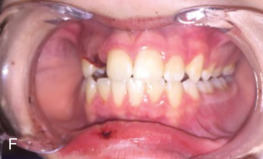

An accurate maxillofacial examination is only possible following adequate exposure, which includes cleaning the patient’s face and wound. Given the vascularity of the maxillofacial region, blood and debris from even minor soft tissue lacerations can misrepresent the severity of injury. Proper cleaning and examination of wounds may require sedation or general anesthesia to ensure patient comfort. A standard set of photographs should be obtained of patients sustaining facial trauma ( Fig. 1.18.5 ), including anterior, lateral, submental, intraoral, and wound photographs. These photos provide a baseline examination for medicolegal purposes, allow for a visual tool to describe treatment to the patient, and aid the clinician in forming the definitive treatment plan. This chapter will focus on the examination of the oral cavity and mandibular function.